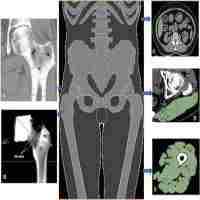

| Abstract | In this study, a model of femur which resembles bone natural structure has been developed. The model initially consists of a solid shell representing cortical bone encompassing a cubical network of interconnected rods with circular cross-sections representing trabecular bone part. A computational efficient program has been developed which iteratively changes the structure of trabecular bone by keeping the local stress in the structure within a defined stress range. The stress is controlled by either enhancing existing beam elements or removing beams from the initial trabecular frame structure. Trabecular bone structure is obtained for two load cases: walking and stair climbing. The results show that as the magnitude of the loads increase, the internal structure gets denser in critical zones. The higher density is achieved using loading associated with the stair climbing. Walking which is considered as the routine daily activity, results in the less internal density in different regions of the bone. The results show that the converged bone architecture consisting of rods and plates are consistent with the natural bone morphology of femur. Furthermore, the bone volume fraction at the critical regions of the converged structure is in a good agreement with previously measured data obtained from combinations of Dual X-ray Absorptiometry (DXA) and Computed Tomography (CT). |